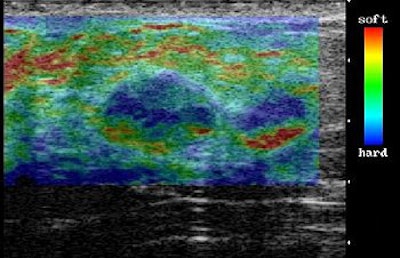

![]() |

| On elasticity image, hypoechoic lesion shows mosaic pattern of green and blue. Figure 3. Ako Itoh A, Ueno E, Tohno E, et al, "Breast Disease: Clinical Application of US Elastography for Diagnosis" (Radiology 2006;239:341-350). |